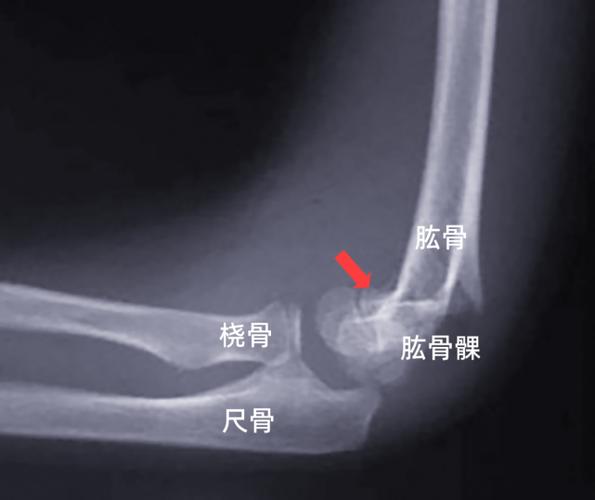

肱骨干与肱骨髁

肱骨干与肱骨髁,肱骨髁间骨折

肱骨近折端向前下移位,远折端向上移位,为伸直型肱骨髁上骨折表现.